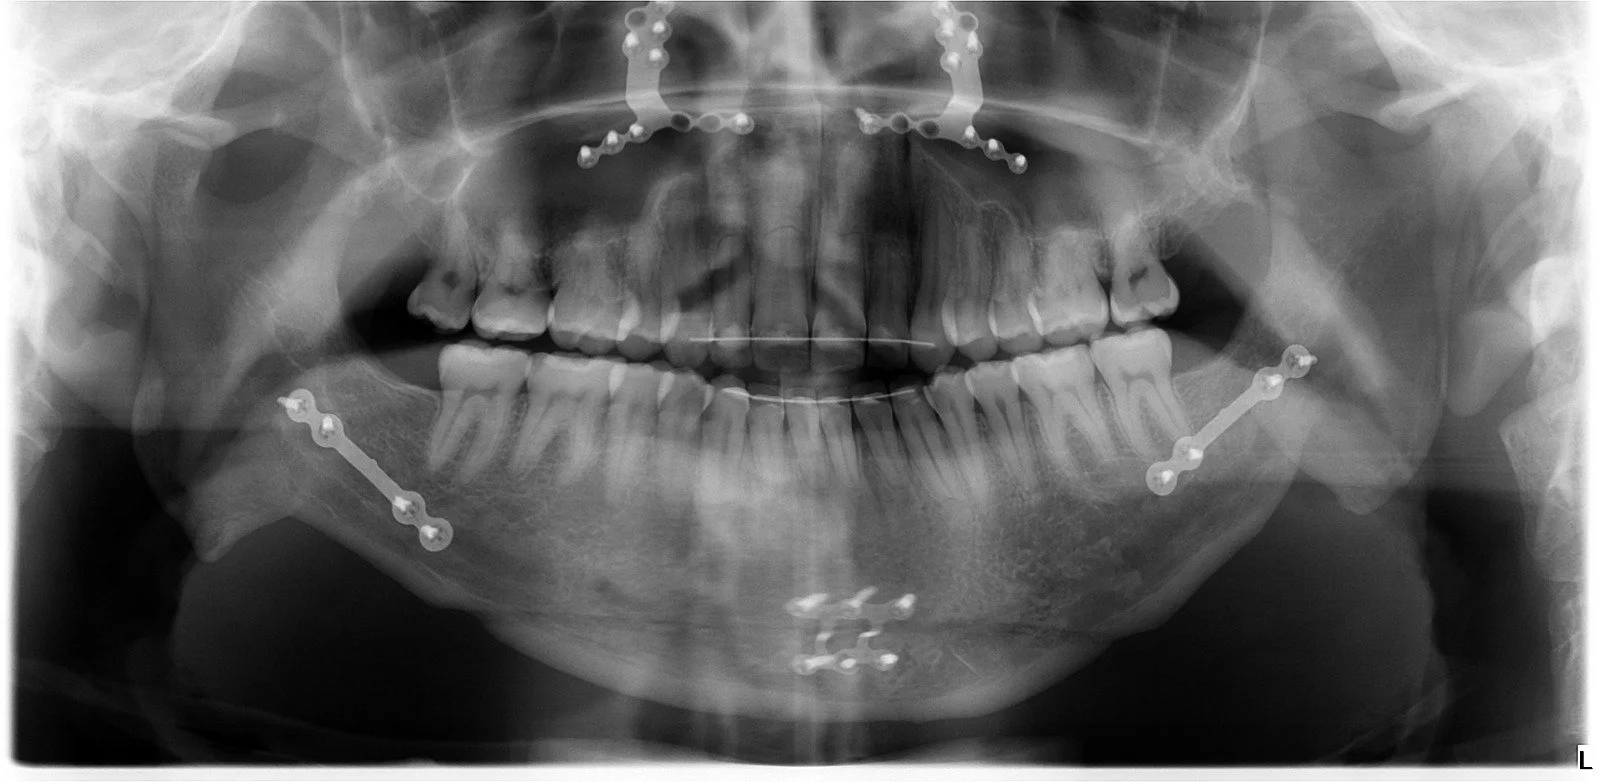

Actualmente la Ortodoncia se realiza a cualquier edad para mejorar la salud bucal, la función masticatoria y la estética, al conseguir un buen alineamiento de los dientes y una relación ósea intermaxilar adecuada con una oclusión normal, por lo que recomendamos hacer una revisión de ortodoncia por lo menos desde los 6 años de edad si no se detecta nada antes.

En la clínica realizamos Ortodoncia Infantil sobre los dientes incluso cuando aún están erupcionando, y a veces con ortopedia de los huesos maxilares para controlar y dirigir su crecimiento, actualmente con alineadores transparentes que incorporan ortopedia.

La Ortodoncia de Adultos trata de mejorar la oclusión y la posición de los dientes incluso con problemas periodontales y de rehabilitación protésica compleja, pero intentamos que la ortodoncia no suponga cambios en su sonrisa utilizando aparatos lo más estéticos posible según cada paciente pudiendo emplear Brackets o Alineadores Transparentes